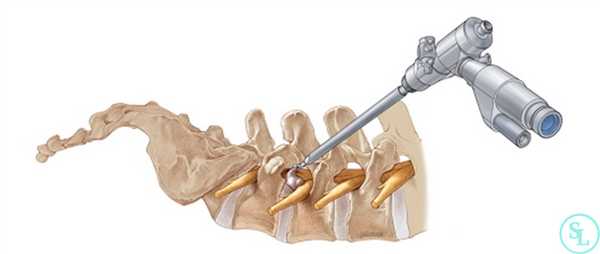

Через них в тело пациента вводится телескопический зонд и эндоскопическая трубка, являющаяся проводником для всего необходимого хирургические инструменты, посредством которых и резецируются измененные ткани в требуемом объеме. Современное оборудование дает возможность добиться высочайшего уровня увеличения операционного поля с высокой четкостью изображения, передающегося с введенной в тело видеокамеры на монитор в режиме реального времени.

- Через разрез в безопасную зону позвоночного пространства вводится расширитель под контролем ЭОП. По нему погружается рабочая гильза, сквозь которую проводят трубку эндоскопа. Ее диаметр составляет 6-8 мм. Подключают светодиод и камеру, моментально начинающую трансляцию изображения на монитор.

Эндоскопический вид

Эндоскопическая операция в нейрохирургии позвоночника применяется сравнительно недавно, за рубежом ее начали внедрять в средине 90-х, в России только спустя 10 лет. Эндоскопия по поводу декомпрессии - это самая миниинвазивная методика резекции патологических тканей через незначительный разрез (1-1,5 см) с использованием телескопического зонда и комплекта инструментов, которые вводятся в его рабочую полость. Сеанс длится в среднем 45 минут. На реабилитацию уходит примерно 60 суток.

Методика, когда хирург производит резекционные мероприятия через тонкую эндоскопическую трубку диаметром всего в 6-8 мм, является наиболее корректной по отношению к здоровым кожным и окружающим мышечно-связочным структурам. Благодаря этому пациент легче и быстрее переносит восстановительные этапы.

- В созданное отверстие под контролем ЭОП в безопасную зону позвоночного пространства вводится дилататор (расширитель), затем по нему вводится рабочая гильза, и уже через гильзу устанавливают трубку эндоскопа. В основном приборе подключают камеру и световод.